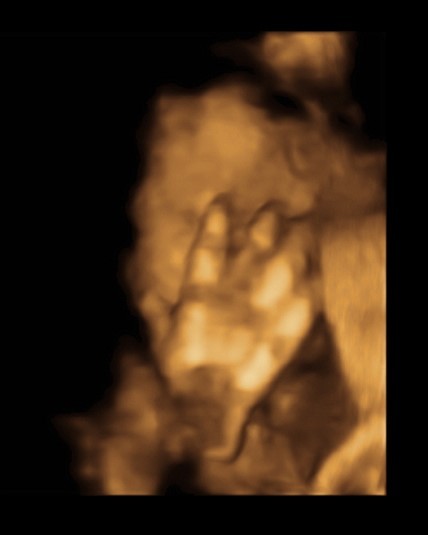

- Dr. Suveică Radu - Obstetrică-ginecologie, Ecografie obstetricală şi ginecologică; Histeroscopie; Chirurgie laparoscopică ginecologică